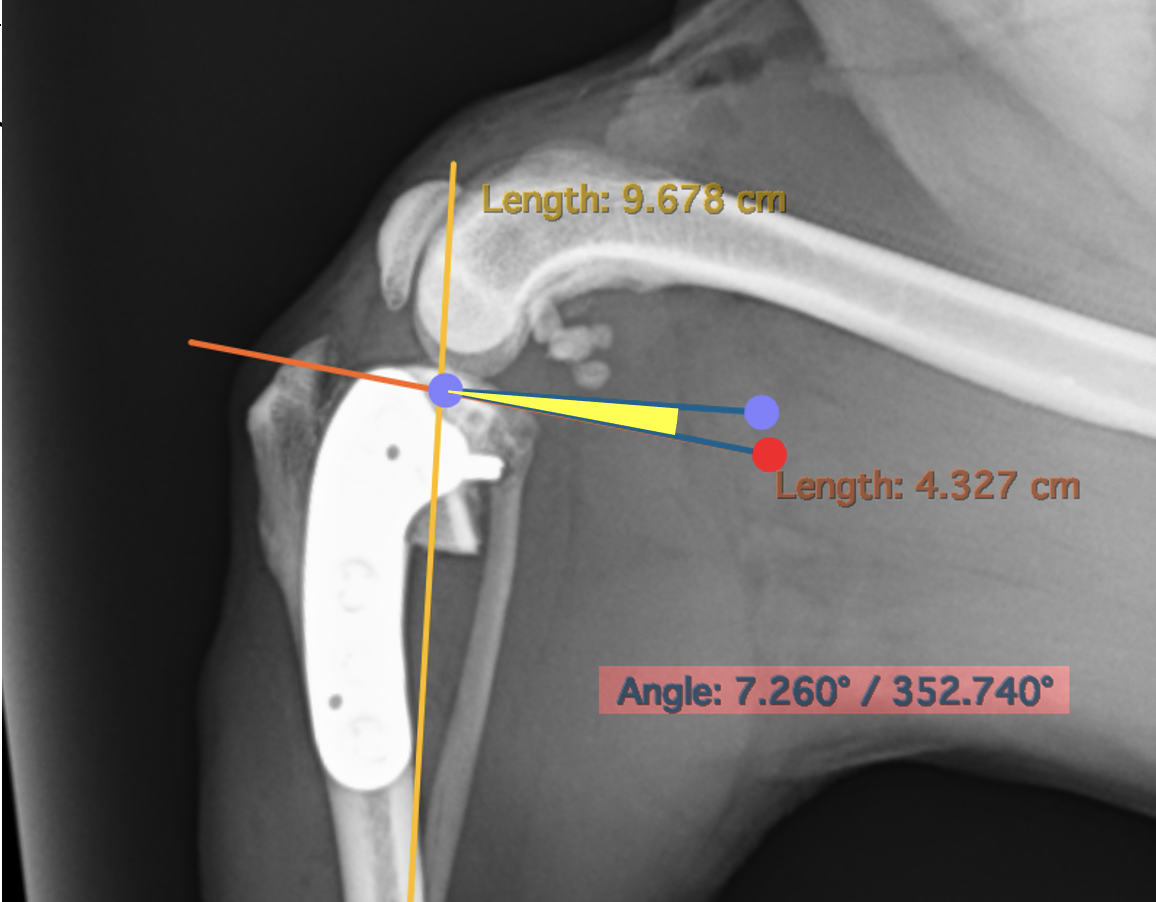

黄色部分がTPAと呼ばれる角度で32度程度あることがわかります。円が描いてあるのはそこで骨を切る計画を示しており、そのほかの長さはその縁の位置を決めるための指標となっています。

TPLOの術後のレントゲンです。約7度になっており、計画通りに手術が行えています。脛骨のずれ(CrTT)も消失しているのがわかると思います。 このように、円形に切ることで、膝の回転中心をずらすことなく骨を矯正できるため、骨短長がほとんどなく(長さが変わりません)、荷重のズレを少なくすることができます。